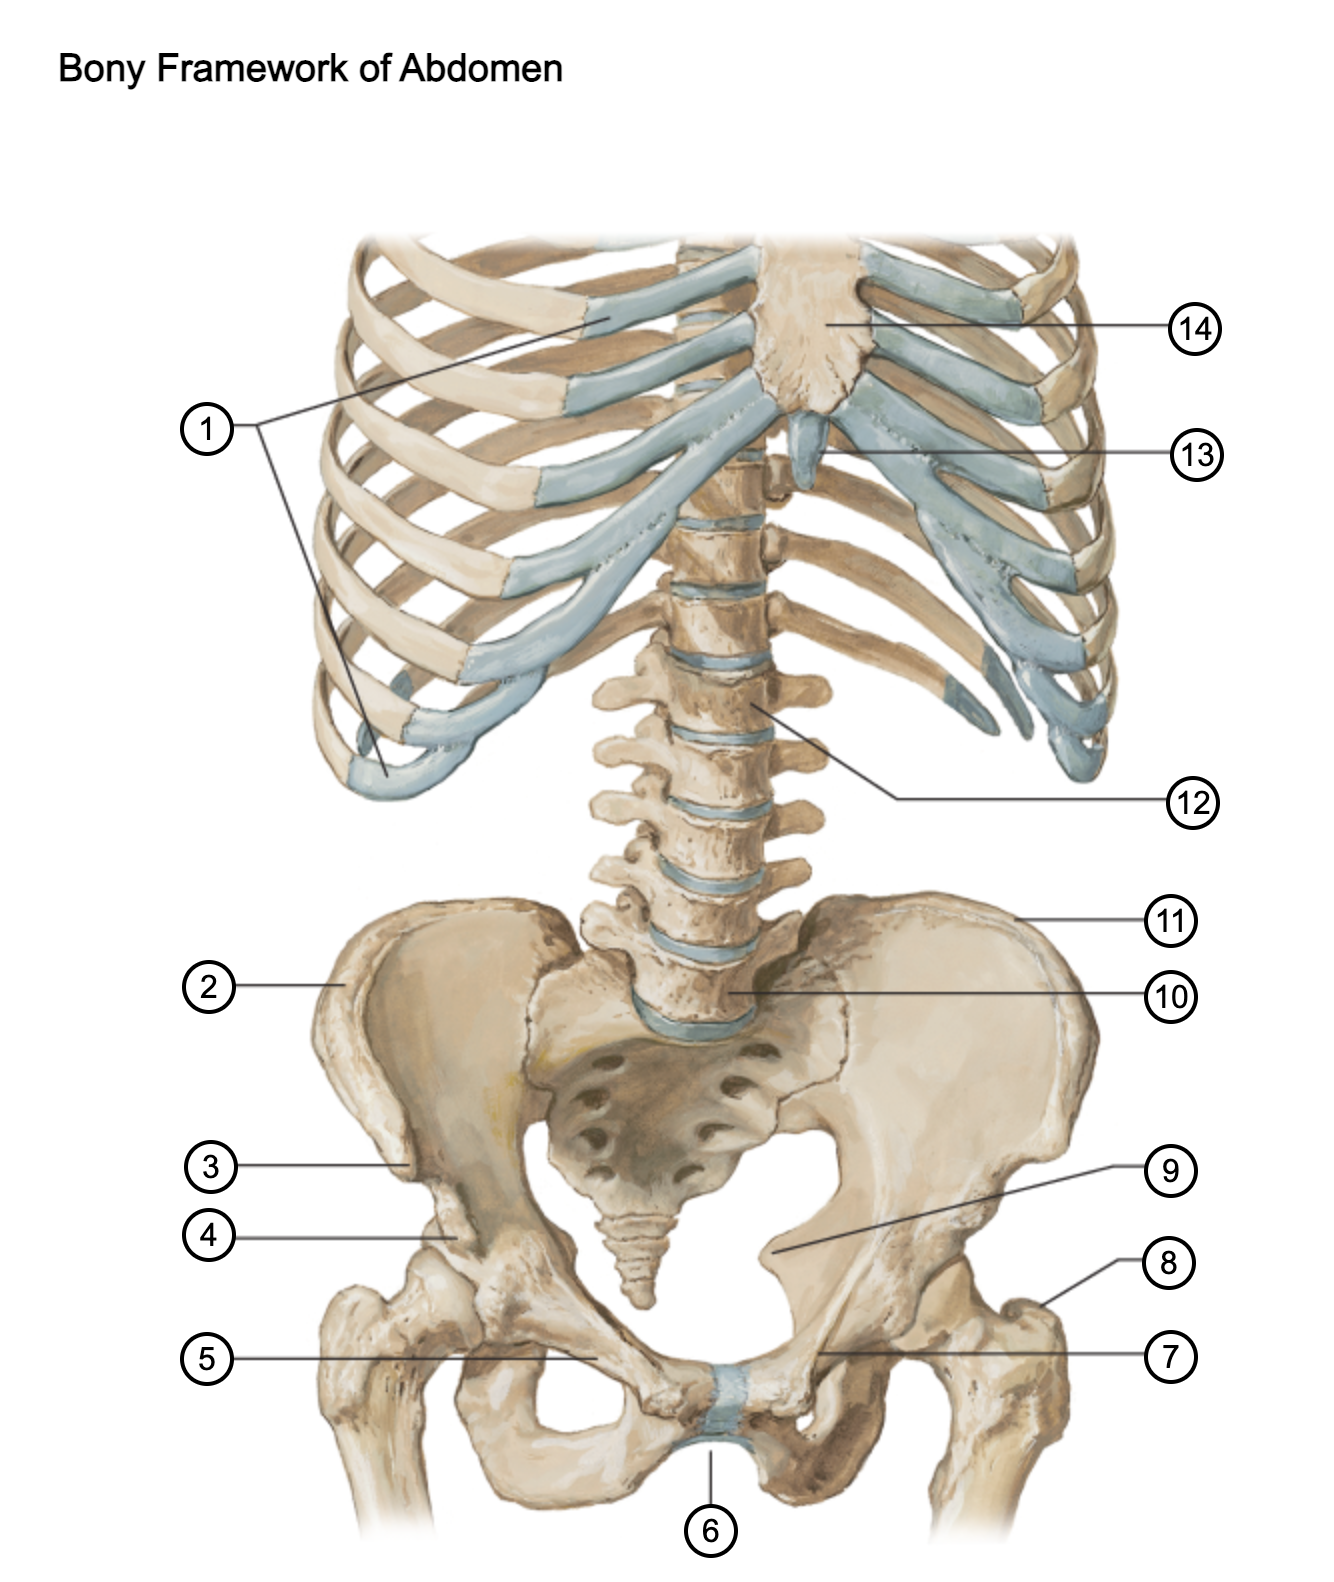

1

costal cartilages

2

iliac crest

3

anterior superior iliac spine

4

anterior inferior iliac spine

5

superior pubic ramus

6

pubic arch

7

pecten pubis

8

greater trochanter

9

ischial spine

10

L5 vertebra

11

iliac crest

12

L1 vertebra

13

xiphoid process

14

body of sternum